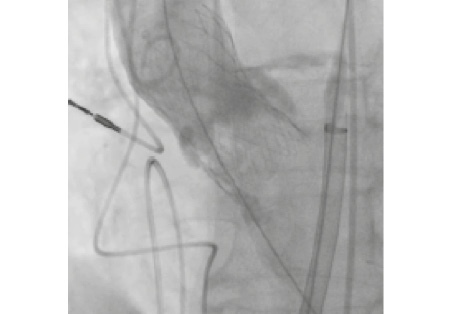

На системе доставки имплантирован биопротез CoreValve Evolut R 29 мм, последовательно выполнена постдилатация баллонами 20 и 23 мм. При контрольной ЧпЭхоКГ флотирующий элемент не визуализируется (рис. 5, б). При финальной КАГ коронарные артерии проходимы, запирательная функция протеза АК осуществляется в полном объеме (рис. 6).

Рис. 6. Контрольная ангиография.